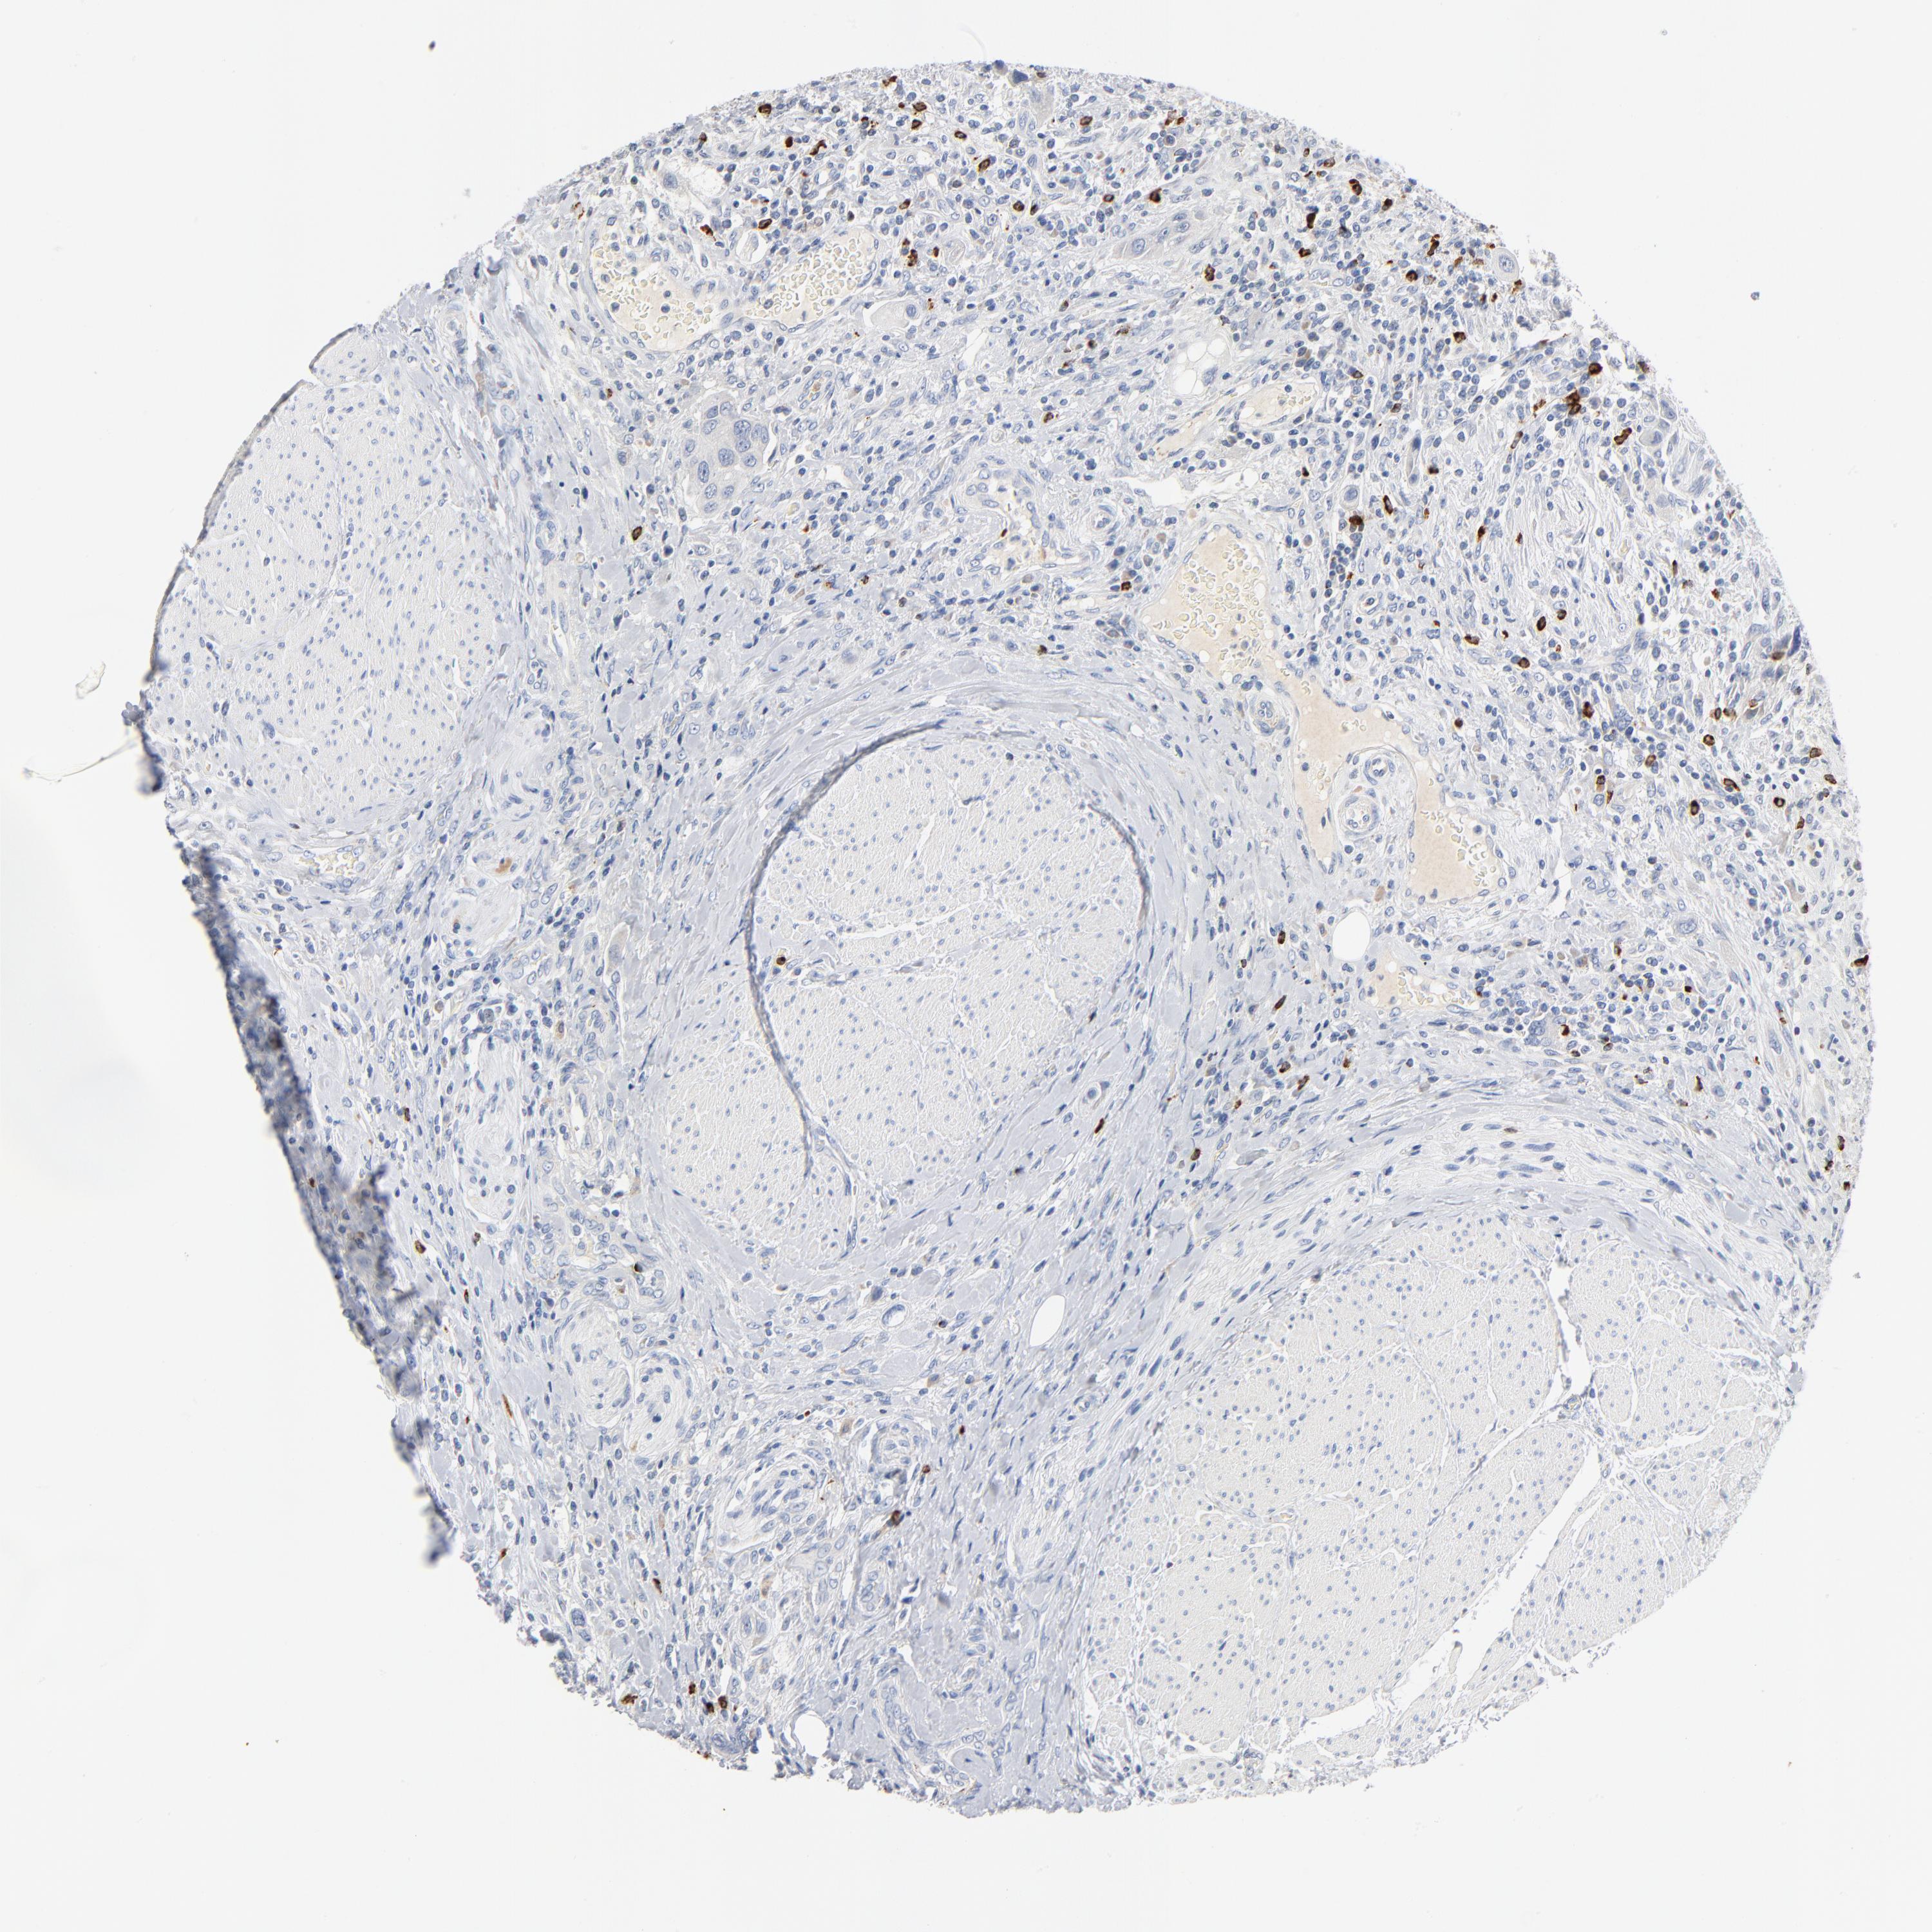

UROTHELIAL CANCER - Protein expressioni

A mouse-over function shows sample information and annotation data. Click on an image to view it in a full screen mode. Samples can be filtered based on level of antibody staining by selecting one or several of the following categories: high, medium, low and not detected. The assay and annotation is described here.

Note that samples used for immunohistochemistry by the Human Protein Atlas do not correspond to samples in the TCGA dataset.

Antibody stainingi

Antibody staining in the annotated cell types in the current human tissue is reported as not detected, low, medium, or high, based on conventional immunohistochemistry profiling in selected tissues. This score is based on the combination of the staining intensity and fraction of stained cells.

Each image is clickable and will lead to virtual microscopy that enables deeper exploration of all samples and also displays staining intensity scores, fraction scores and subcellular localization as well as patient and tissue information for each sample.

Antibody HPA003418

Antibody CAB000376

Urothelial carcinoma, High grade

Urothelial carcinoma, Low grade